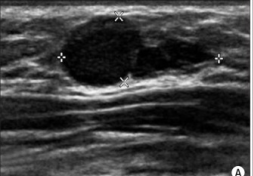

Radial Scar

Radial scars (complex sclerosing lesions) are hardened areas of breast tissue surrounded by abnormal ducts and tissue structures. Most radial scars are found on mammograms. As they resemble cancer, they require core biopsy for testing. Surgical excision is often recommended to confirm the surrounding tissue is normal. A referral to a breast surgeon is required for further investigation.

Pictorial essay: Breast USG by G. Shah and B. Jankharia is licensed under CC BY 2.0